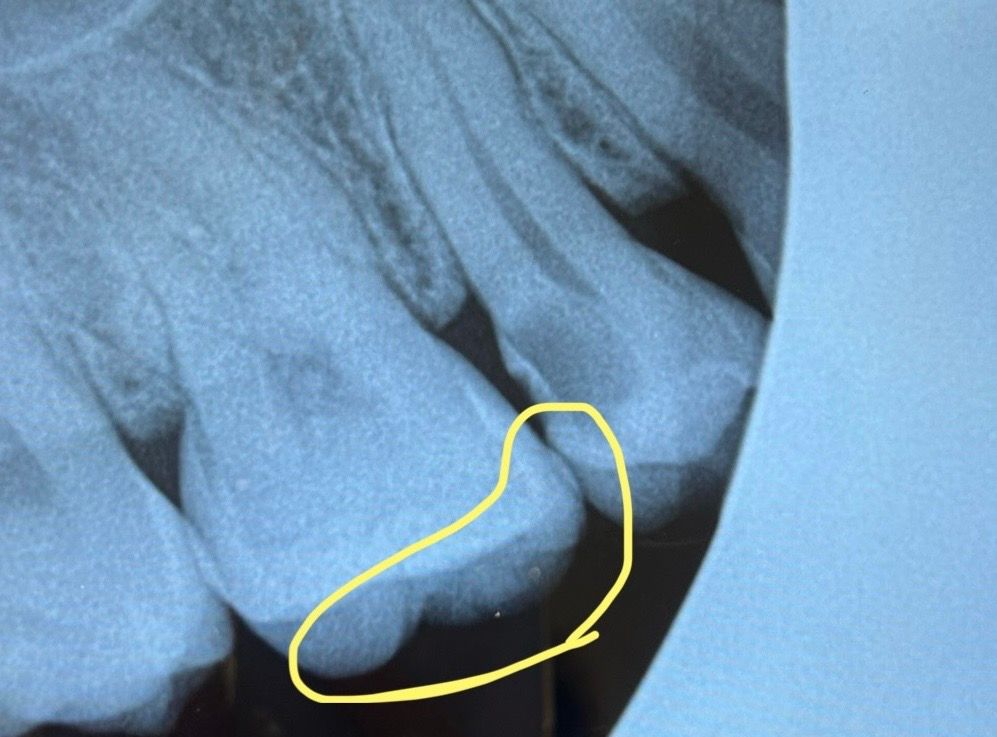

신경치료, 인레이 꼭 해야하나요? (엑스레이 유)

이쪽 치아는 딱봐도 까맣긴한데

많이 썩은건가요?

이쪽이 단거 찬거 먹을 때 시리고

저녁에 자발통도 심했어요

보여주신 사진 상에서 앞쪽은 이미 신경이 노출되어 신경치료를 진행해야 하며 신경치료 이후에는 남아 있는 치아를 보호하기 위해 크라운을 씌워야 합니다. 또한 충치 부위가 크므로 반드시 크라운을 하셔야 할 것으로 보입니다. 뒤쪽 치아는 앞쪽 치아의 사이가 충치가 생긴 것이므로 해당 부분을 확인하고 충치가 있다면 인레이를 할 필요가 있어 보입니다.

첫번째 사진의 치아는 충치가 많이 진행되서 신경치료를 하셔야될꺼 같고, 옆치아의 경우 옆면 충치가 넓거나 깊으면 인레이 간단하면 레진으로 하기도 합니다.

자발통이 이미 있는 경우라면 비가역적 치수염의 상태이고 이런경우 신경치료는 불가피합니다